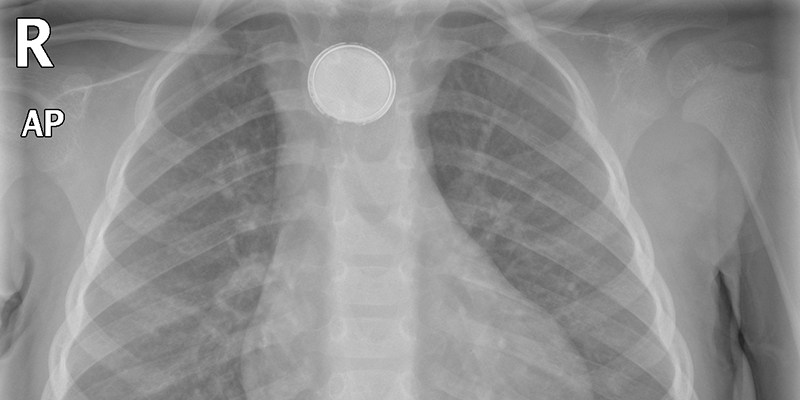

Tussen 2002 en 2016 verdrievoudigde het aantal 0- tot en met 4-jarige kinderen die een batterij hadden ingeslikt. Meestal gaat het om kleine knoopcelbatterijen die afkomstig zijn uit geopende verpakkingen, lampen en speelgoed. Veruit de meeste batterijtjes verlaten het lichaam via de normale weg, maar sommige blijven in de slokdarm of maag steken. Dan kunnen ernstige complicaties optreden. Hoe vaak komt dit voor, wat zijn de risicofactoren en waaruit bestaat de behandeling?